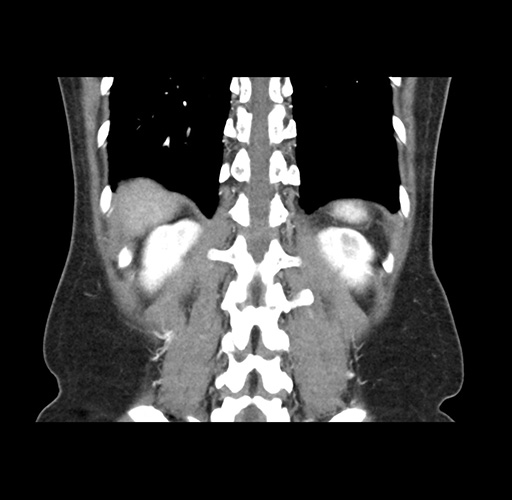

Imaging Analysis

Look through the patient's CT scan to identify any areas of concern for the necessary procedure.

Based on your CT findings, which issue(s) would give reason for "planned slowing down moment(s)" in this case?

Considering a standard left lateral sectionectomy procedure, what step(s) of the operation would you do differently in this case ?